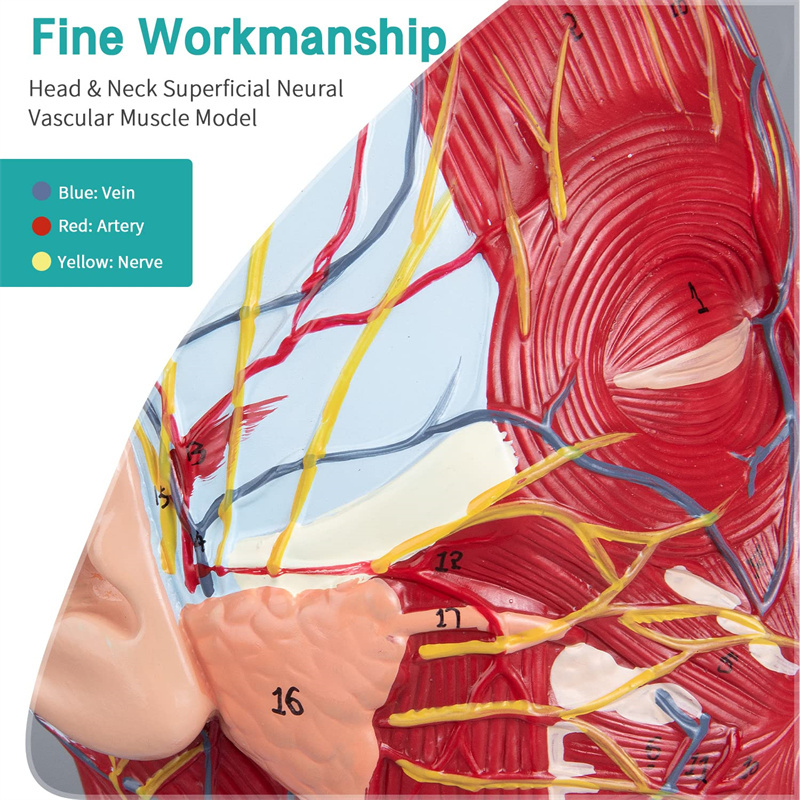

【1: 1 ਦਾ 1 ਜੀਵਨ ਬਚਾਉਣ ਵਾਲਾ ਹਿੱਸਾ 1: 1 ਕੁਦਰਤੀ ਵੱਡੇ ਸਿਰ ਅਤੇ ਗਰਦਨ ਸਤਹੀ ਸੰਚਾਲਕ ਨਾਚਲਣ ਮਾਸਪੇਸ਼ੀ ਮਾਡਲ (ਸੱਜੇ ਪਾਸੇ). ਵਧੀਆ ਕਾਰੀਗਰ. ਐਨਾਟੋਮਿਕਲ ਵਿਸ਼ੇਸ਼ਤਾਵਾਂ ਦੀ ਪੂਰੀ ਸ਼੍ਰੇਣੀ ਦੀ ਪੇਸ਼ਕਸ਼.

【ਉੱਚ ਕੁਆਲਟੀ】 ਦਿਮਾਗ ਦੇ ਸਰੀਰ ਵਿਗਿਆਨਕ ਮਾਡਲ, ਗੈਰ-ਜ਼ਹਿਰੀਲੇ ਵਾਤਾਵਰਣ ਦੇ ਅਨੁਕੂਲ ਪੀਵੀਸੀ ਸਮੱਗਰੀ ਦਾ ਬਣਿਆ, ਸਾਫ ਕਰਨਾ ਅਸਾਨ ਹੈ. ਸਰੀਰ-ਚਿੱਤਰ ਨੂੰ ਹੱਥ ਨਾਲ ਪੇਂਟ ਕੀਤਾ ਜਾਂਦਾ ਹੈ ਅਤੇ ਵੇਰਵੇ ਵੱਲ ਪੂਰਾ ਧਿਆਨ ਨਾਲ ਇਕੱਠਾ ਕੀਤਾ ਜਾਂਦਾ ਹੈ.

【ਸਤਹੀ ਨਿ ur ਰੋਵਸਕੂਲਰ ਮਾਸਪੇਸ਼ੀ ਦਾ ਮਾਡਲ】 ਉੱਚਿਤ ਵਿਸਥਾਰਪੂਰਕ, ਨੰਬਰ ਮਾਰਕ ਕੀਤੇ, ਕੰਬਦੇ ਕੰ the ੇ, ਨਾੜੀ ਅਤੇ ਗਰਦਨ ਦੇ ਅੰਦਰੂਨੀ structures ਾਂਚਿਆਂ ਦੀ ਸਮਝ ਨੂੰ ਡੂੰਘਾ ਕਰੋ. ਲਾਲ-ਧਮਣੀ, ਨੀਲੀ-ਨਾੜੀ, ਪੀਲੇ-ਨਸ.

【ਵਿਸ਼ੇਸ਼ਤਾਵਾਂ】 ਦਾ ਸਾਹਮਣਾ ਕੀਤੇ ਚਿਹਰੇ ਦੀਆਂ ਸਤਹੀ ਮਾਸਪੇਸ਼ੀਆਂ ਨੂੰ ਦਰਸਾਉਂਦਾ ਹੈ; ਸਤਹੀ ਖੂਨ ਦੀਆਂ ਨਾੜੀਆਂ ਅਤੇ ਚਿਹਰੇ ਦੀਆਂ ਨਾੜੀਆਂ ਅਤੇ ਖੋਪੜੀ; ਪੈਟੀਡ ਗਲੈਂਡ ਅਤੇ ਵੱਡੇ ਸਾਹ ਦੀ ਨਾਲੀ ਦੇ ਅੰਦਰੂਨੀ structures ਾਂਚਿਆਂ; ਸਰਵਾਈਕਲ ਰੀੜ੍ਹ ਦੀ ਸੋਗਿਤਲ ਕਰਾਸ-ਸੈਕਸ਼ਨ structure ਾਂਚਾ.

ਇਹ ਮਾਡਲ ਇੱਕ ਕੁਦਰਤੀ ਵੱਡਾ ਸਿਰ ਅਤੇ ਗਰਦਨ ਸਤਹੀ ਨਿ ur ਰੋਵਸਕੁਲਰ ਮਾਸਪੇਸ਼ੀ ਮਾਡਲ, 1 ਕੰਪੋਨੈਂਟ, ਚਿਹਰੇ ਅਤੇ ਖੋਪੜੀਆਂ ਦੇ ਸਤਹੀ ਮਾਸਪੇਸ਼ੀਆਂ ਦੇ ਵੇਰਵੇ ਦਿਖਾਉਂਦੇ ਹੋਏ, ਨਸਾਂ ਅਤੇ ਪੈਰੋਟਿਡ ਗਲੈਂਡ ਅਤੇ ਵੱਡੇ ਸਾਹ ਦੀ ਨਾਲੀ ਦਾ ਮੈਡੀਅਲ ਬਣਤਰ, ਅਤੇ ਸਰਵਾਈਕਲ ਰੀੜ੍ਹ ਦੀ ਸੋਗਟਲ ਸੈਕਸ਼ਨ ਦਾ structure ਾਂਚਾ